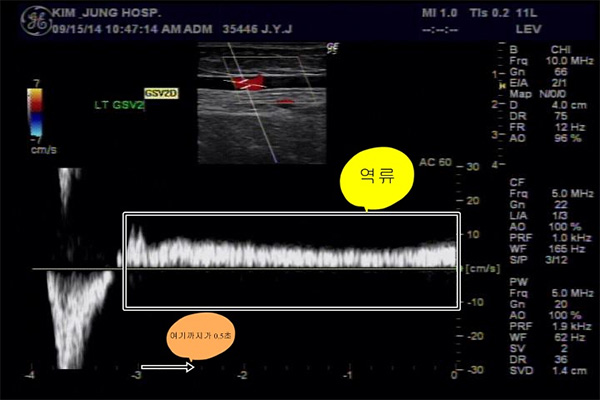

일방통행 밸브가 망가져 심장으로 일부의 피가 가기는 하지만 대부분의 혈류가 망가진 밸브를 통해 다시 다리로 내려와 정맥혈관이 계속 커지고 부풀게 되어 정맥류를 형성한다.

서 있을 때 망가진 밸브로 통해 피가 밑으로 고이면서 정맥압이 상승되어 여러 증상들이 나타날 수 있다. 혈관의 확장으로 미용상 보기가 흉하고, 만성적인 다리통증, 하지 피로감, 무거운 느낌, 저린감, 부종 야간의 장딴지 경련(쥐가 잘남)오래되면 주변 피부가 헐고 궤양이 생기며 혈전정맥염이 생길 수 있습니다.